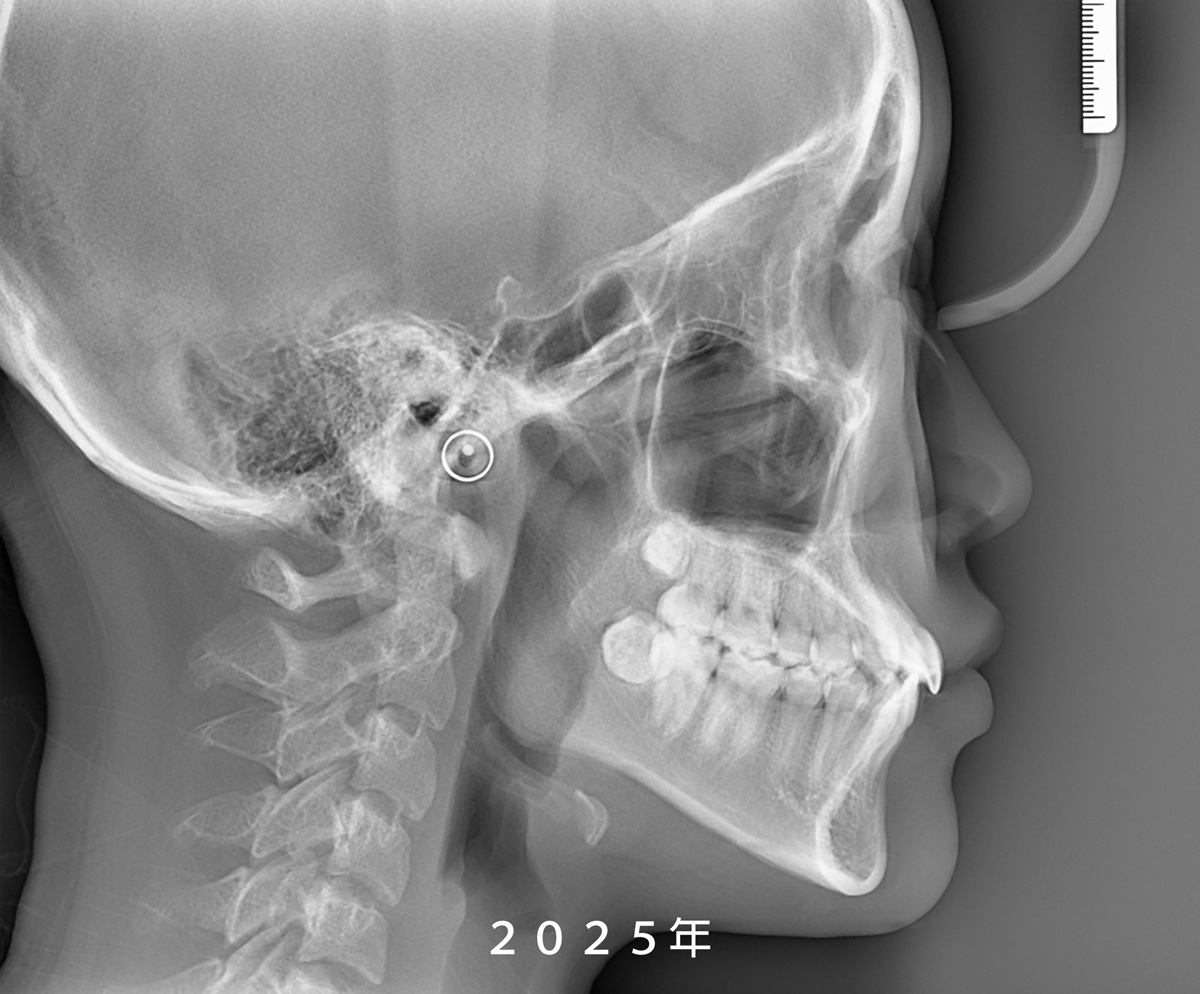

從 X 光片重疊影像可以發現,

她的鼻子與下巴都有明顯的成長變化,

但所幸前牙並未發展成

我們較為擔心的反咬(negative overjet)問題。

Because the pandemic reduced Yun’s visit frequency for nearly two years, it unexpectedly gave us a clearer window into her jaw growth. Superimposed X-rays showed noticeable changes in both her nose and chin, but thankfully her front teeth never shifted into a negative overjet, which is a common concern in skeletal Class III cases.